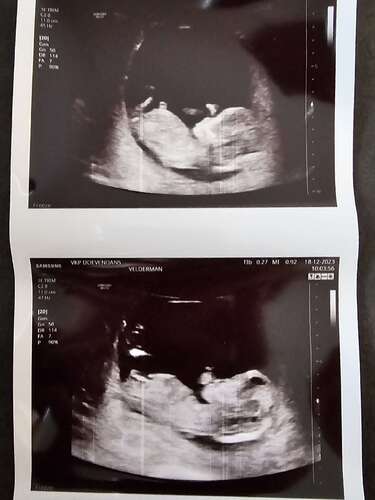

Wat denken jullie? Ik kan maar 1 foto plaatsen. Ik post in mijn volgende bericht nog een foto daar lijkt het weer heel anders

Nog een foto naar aanleiding van vorige bericht. Hier ziet het er weer anders uit dan de vorige foto